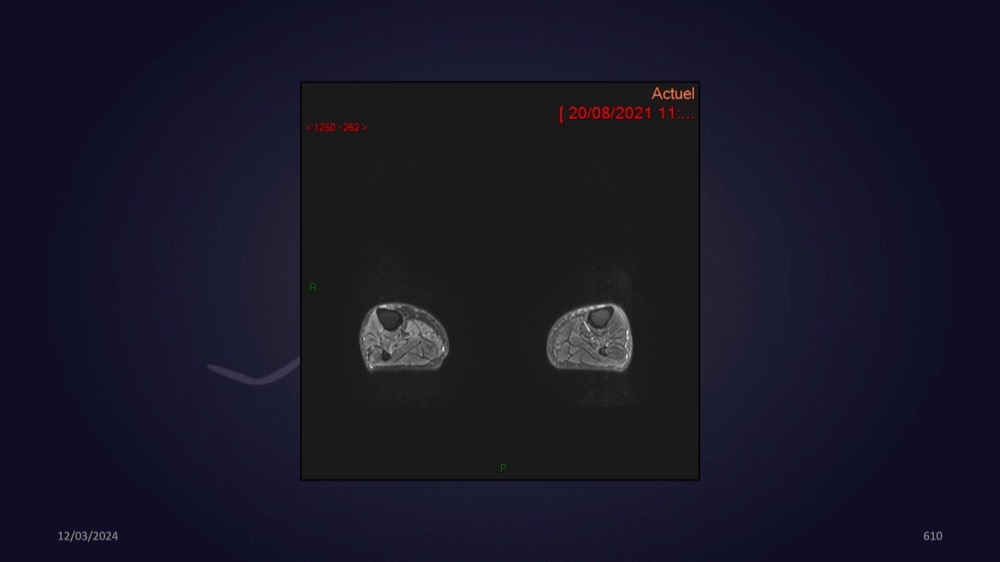

Mezhgani / Dimitri Boulos / Carlier 23/03/2022